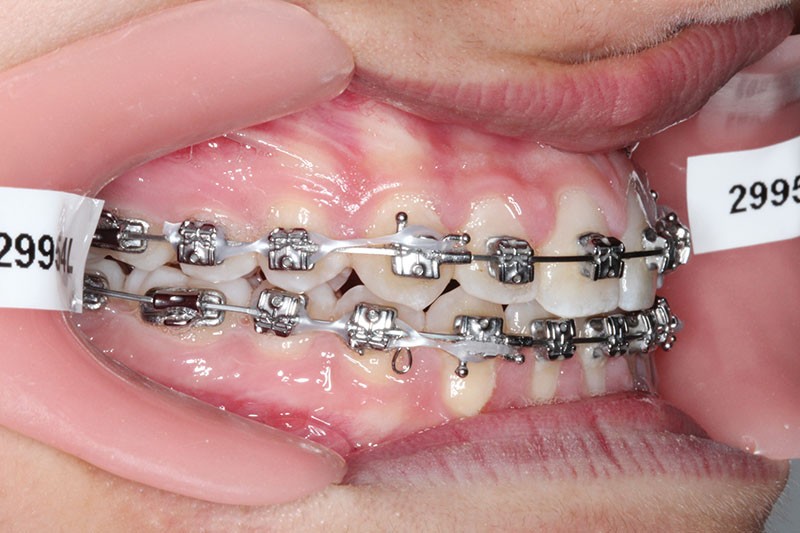

2e phase : mise en place du système multibague Carriere SLX (fig. 7 à 9)

Nous continuons le port des élastiques…